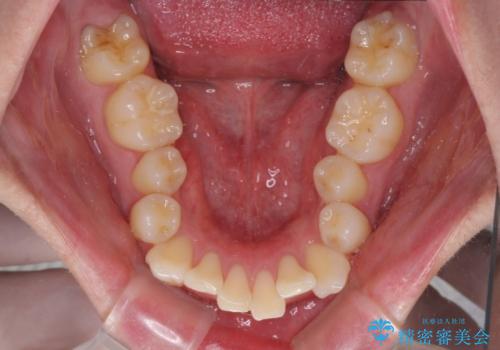

- 八重歯を気にして来院された患者様です。

顕著な上顎の八重歯とディープバイトであったため、上顎の左右第一小臼歯を抜歯することとしました。

犬歯歯根の位置や奥歯の咬み合わせから、ワイヤー装置での治療を強くおすすめいたしましたが、ご本人の強い希望により、妥協的な仕上がりとなることを了解いただき、インビザラインにて矯正治療を行うこととしました。

インビザライン単体で、左右ともに移動の難しい位置に歯根のある犬歯を整えるのは困難と判断し、補助装置を併用することとしました。